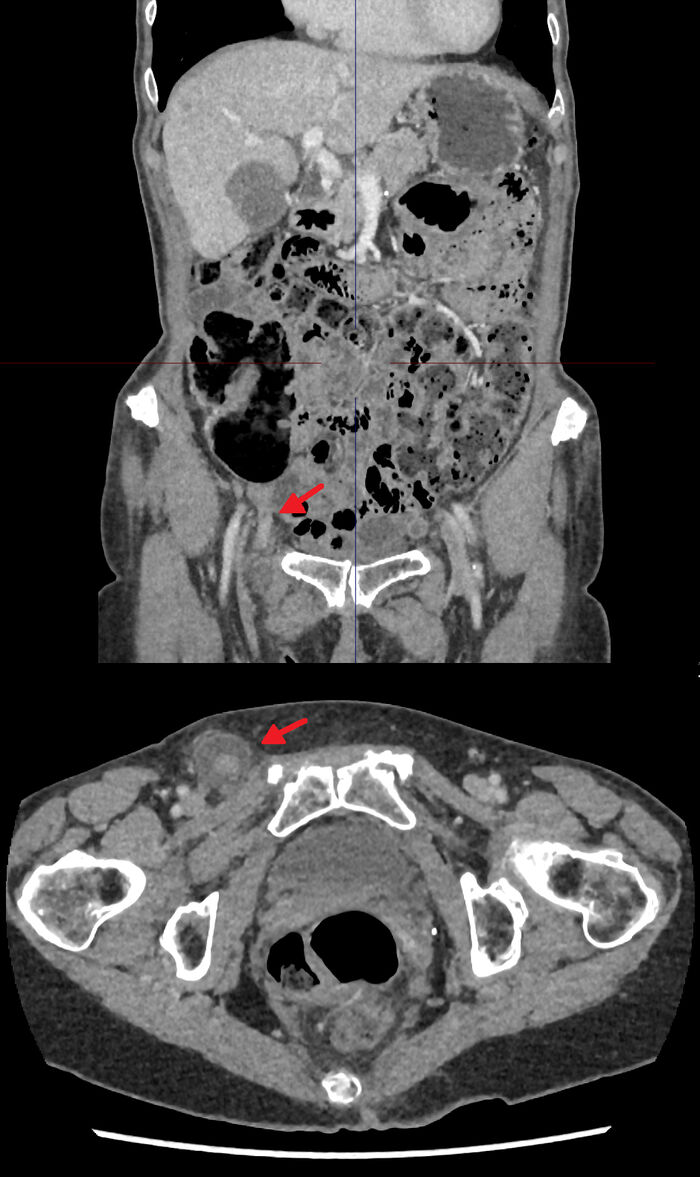

Henni var vísað til mats á kviðarholsskurðdeild vegna tæplega tveggja vikna sögu um fyrirferð í hægri nára ásamt verkjum í neðri hluta kviðar. Hún hafði ekki verið með hita, ógleði eða lystarleysi. Við skoðun var hún ekki bráðveikindaleg að sjá né meðtekin af verk og lífsmörk voru eðlileg. Kviðurinn þreifaðist mjúkur og var eymslalaus en í hægri nára þreifaðist hörð, um það bil þriggja cm stór fyrirferð. Það var ekki roði, hiti né bólga yfir fyrirferðinni en væg eymsli. Tölvusneiðmynd af kviðarholi sýndi nárakviðslit sem innihélt botnlangann. Það sáust einnig bólgumerki og vökvi umhverfis botnlangann (mynd 1).

Mynd 1. Tölvusneiðmynd af kviðarholi sem sýnir læriskviðslitið með kviðslitssekk sem inniheldur botnlangann í ennis- og áslægu sniði (rauð ör).

Eftir að greining lá fyrir var reynt að ýta innihaldi kviðslitsins aftur inn, sem tókst ekki. Hún var tekin samdægurs til opinnar kviðslitsaðgerðar að hætti Nyhus og reyndist þá vera með innklemmt (incarcerated) læriskviðslit. Kviðslitssekkurinn var dreginn til baka úr lærisganginum (femoral canal) og opnaður. Í honum var bólginn botnlangi og því tekin ákvörðun um að fjarlægja hann (mynd 1 og 2).